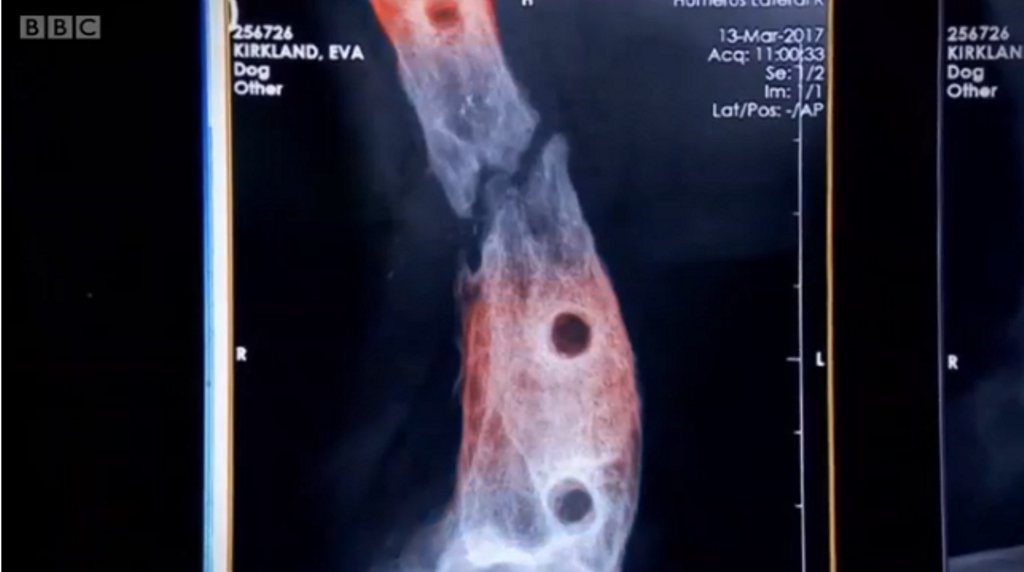

Собака не міг ходити, того як його збила машина і він отримав перелом ноги. Травма була настільки серйозна, що довелося відрізати кінцівку. Проте її врятували науковці, у лабораторії вони виростили з частини кістки – нову.Науковці вкрили частину кістки пластмасою та хімічними речовинами – через 6 тижнів кістка була повністю зцілена. Це перше таке лікування в світі, передає ВВС Україна.